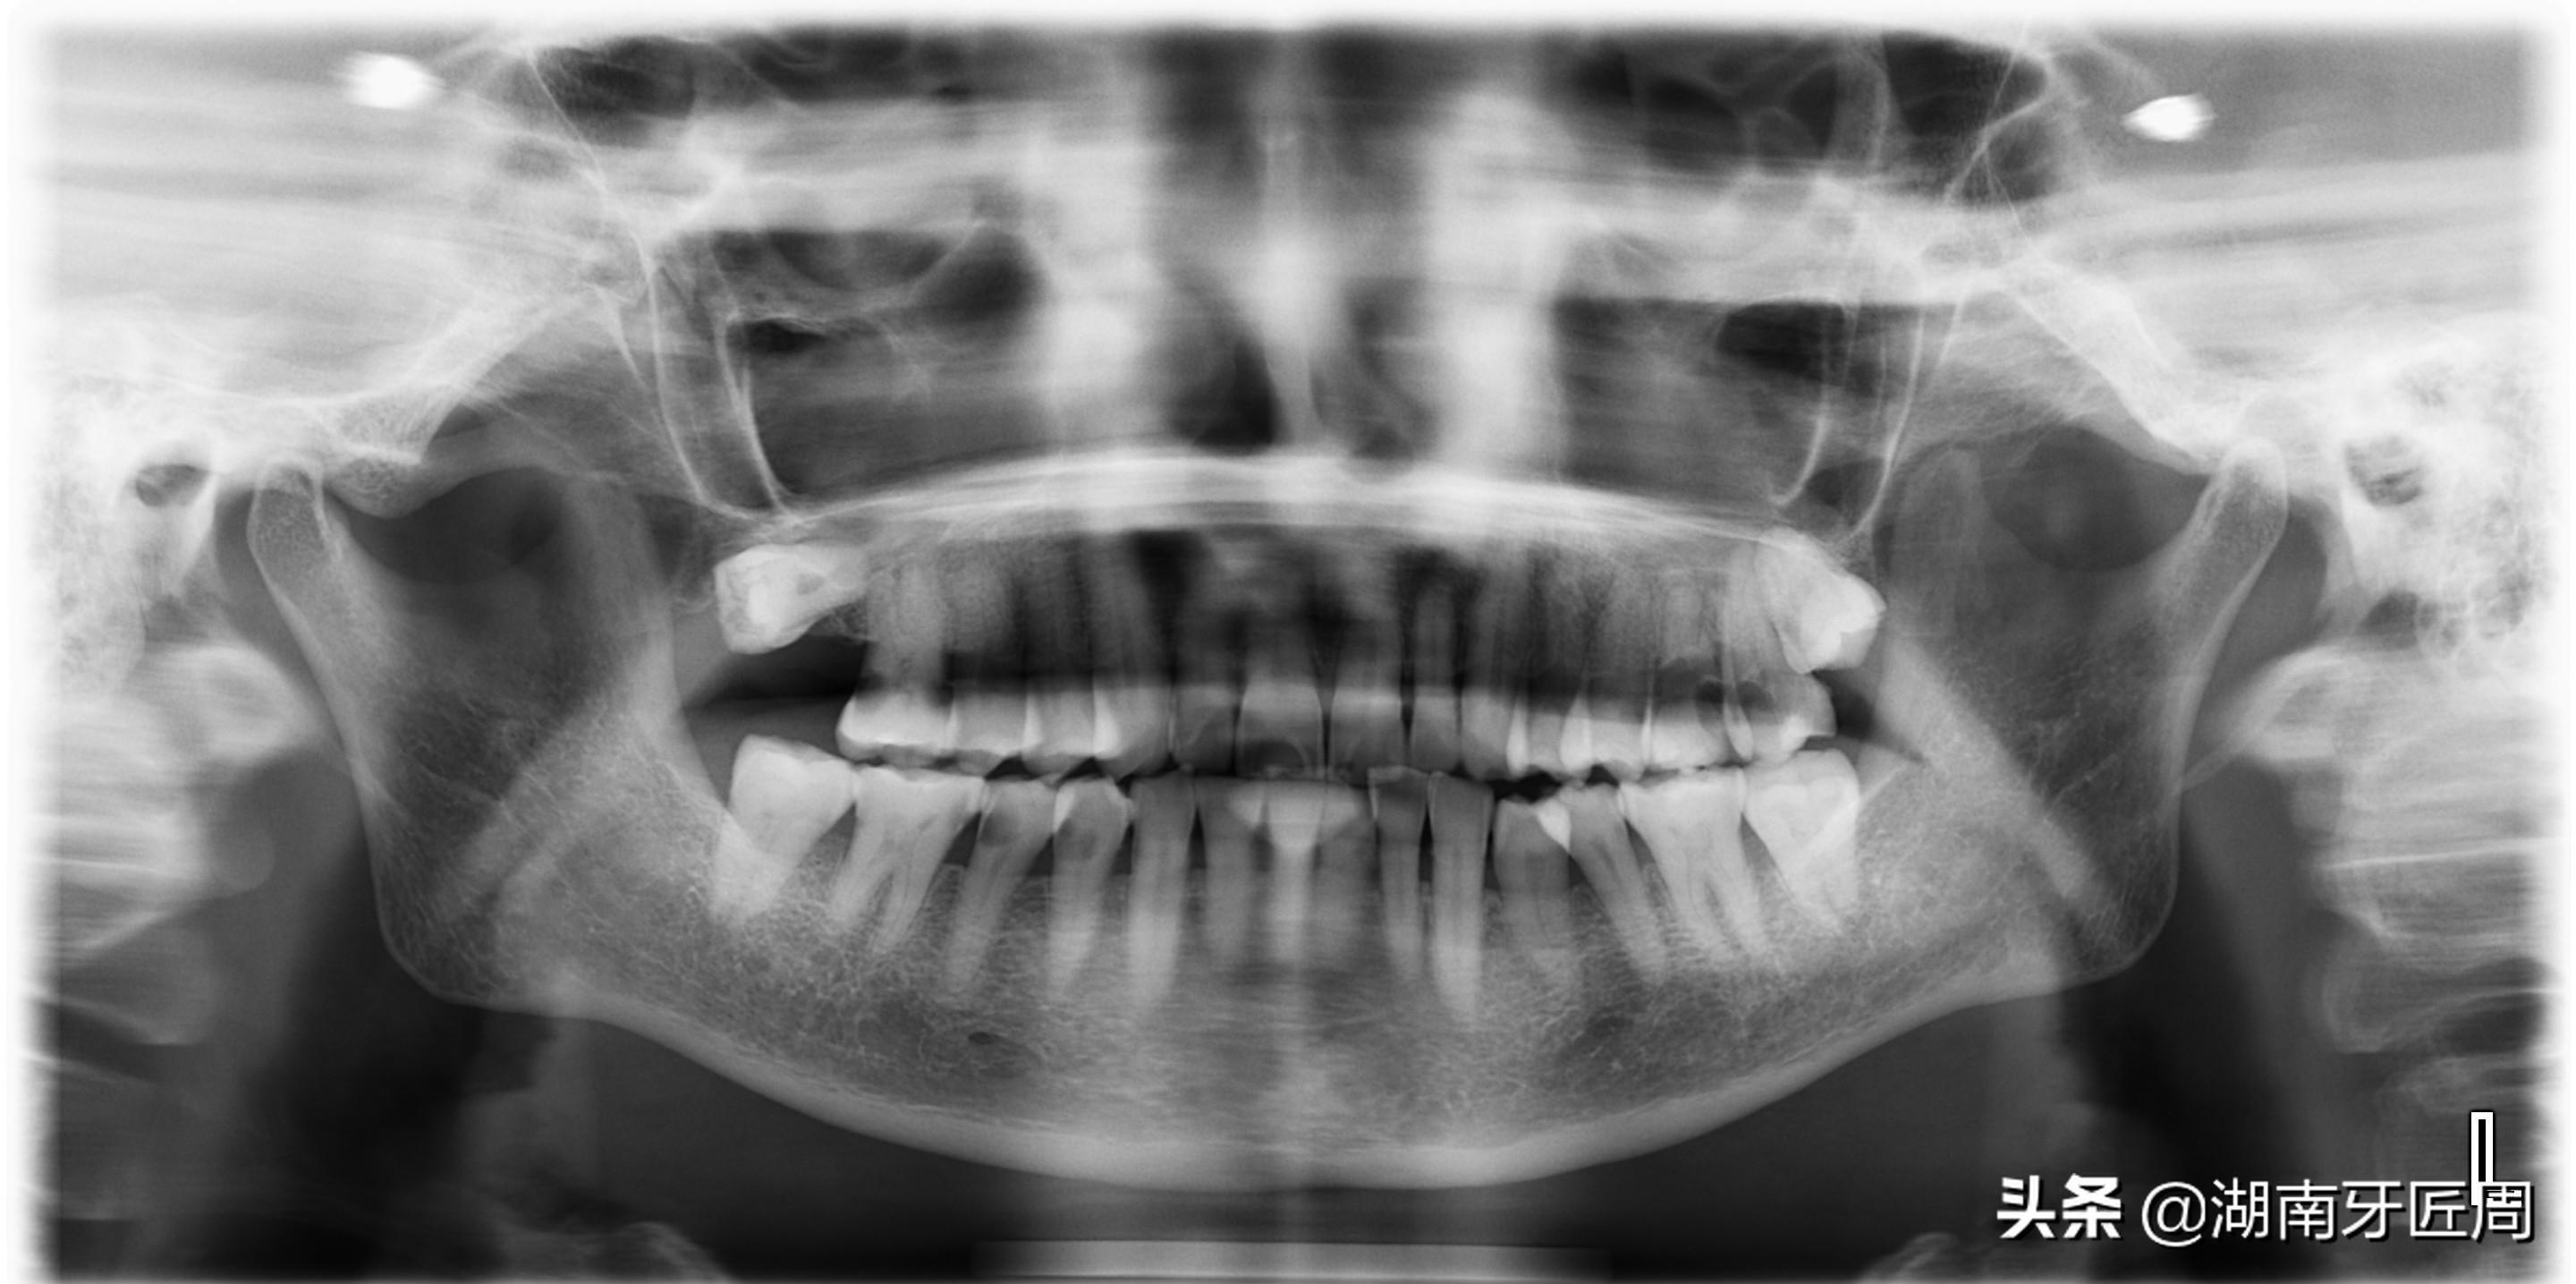

图片7两侧下颌智齿阻生

图片8